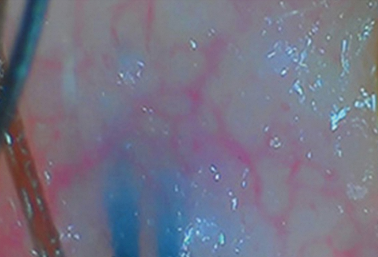

常见头皮问题

COMMON SCALP ISSUES